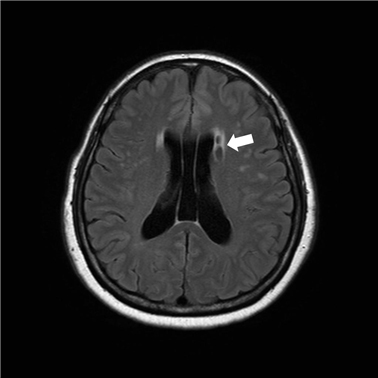

뇌경색 초기증상 모두 정리했어요

이번 포스팅에서 뇌경색 초기증상 모두 알아보려고 해요. 한 번쯤은 뇌경색, 뇌출혈, 뇌졸중에 대해서 들어보신 적이 있을꺼에요.

뇌경색 초기증상이 의심된다면 지금 바로 병원을 내방해 진단을 받고 적절한 치료를 손대는 것이 후유증을 감하는데 중요 해요. 시간이 관건이며, 뇌세포의 괴사, 증상 악화, 너무 늦으면 사망에 이를 수 있는 뇌혈관의 괴사를 피하기 위하여 증상이 나타난 뒤에 4시간 이내에 잘 맞은 약물, 시술 또는 수술을 신속히 실시해야 합니다. 치료로 즉시 하셔야 해요.

현재까지 뇌경색 초기증상에 대하여 알아보았습니다. 뇌경색은 예사로 즉각적인 치료가 필요한 질병으로 자가진단이 쉽지 않다고 하면, 바로 의료기관에 접수한 경우 혹은 아니라면 응급실로 날아가는 것이 좋다고해요.